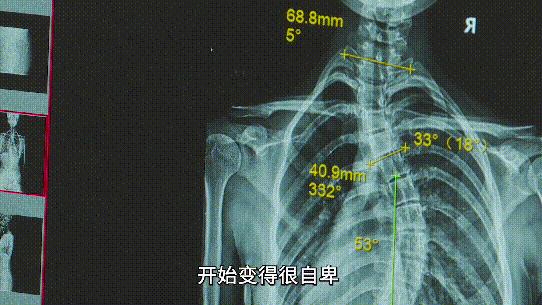

小玉13岁那一年,被诊断出:脊柱S形侧弯。

“我变得很自卑,干什么事情,都觉得别人在看自己。”